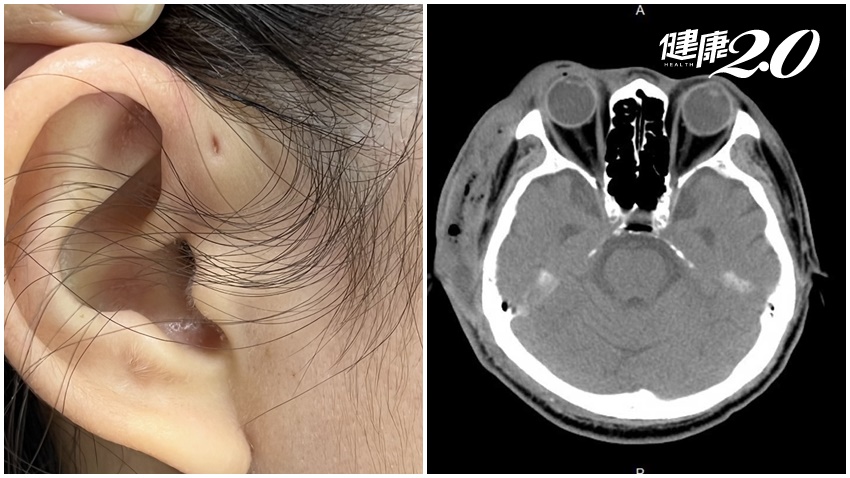

腳趾黑點、傷口不癒要小心!婦截趾保命 手腳皮膚5變化恐是惡性癌

...學附設醫院指出,這名婦人原以為自己的腳趾症狀是慢性甲溝炎,但高醫整形外科主治醫師黃書鴻觀察發現病灶外觀有異狀,立即做皮膚切片...